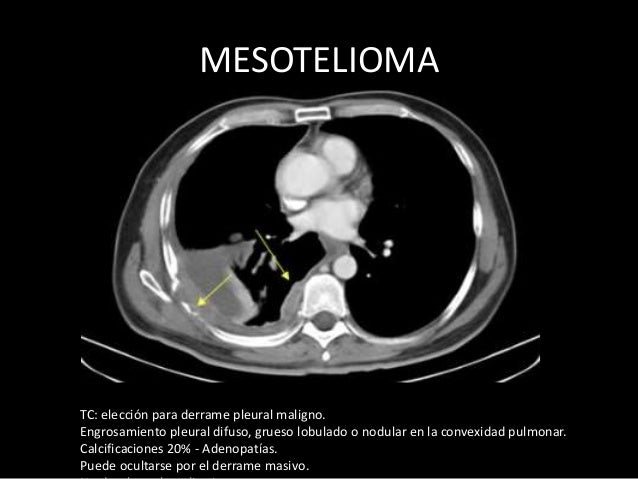

Mesotelioma maligno causa, diagnóstico, pronóstico y tratamiento. El mesotelioma maligno es una neoplasia pleural relacionada con la exposición laboral a amianto, aunque otros factores pudieran estar implicados, con una incidencia en aumento en europa occidental. El dolor torácico y la disnea son sus manifestaciones clínicas más frecuentes.

Mesotelioma maligno medlineplus enciclopedia médica. More mesotelioma maligno pleural images. Derrame pleural bilateral en pacientes sin insuficiencia. Abstract. Background pleural effusion is a frequent disease in the clinic, to which should face not only the internist and the neumologist, but other specialists including general practitioners. Objective to define this type of disease and its different causes.Method fifty cases of bilateral pleural effusion in patients without heart failure diagnosis were presented, studied from 1996 to. Derrame pleural instituto oncoguia. O derrame pleural maligno é uma condição grave e potencialmente fatal que deve ser investigada e tratada de forma eficaz evitando piora do quadro do paciente. Mesotelioma pleural. Causas, diagnóstico y tratamiento.. Cirugía se utilizan 3 tipos de cirugía en el tratamiento del mesotelioma la cirugía diagnóstica. Para obtener una muestra para la biopsia. Se lleva a cabo por toracoscopia o por cirugía pleural abierta. La cirugía paliativa, que incluye la pleurodesis, toracoscopia con pleurodesis y, más raras veces, shunt pleuroperitoneal. Tumor fibroso solitario. Estudio clínicopatológico de 16. Volumen 79, no. 5, septiembreoctubre 2011 419 tumor fibroso solitario discusión el tumor fibroso solitario fue detallado en 1931 por klemperer y rabin1 como una lesión localizada y benigna; una década después, en 1942, stout y murray,5 en estudios ba sados en cultivo de tejidos, sugirieron un origen mesotelial. Mesotelioma wikipedia, la enciclopedia libre. Mesotelioma (o mesotelioma maligno) es una forma rara de cáncer que se desarrolla a partir de células transformadas originarias del mesotelio, el revestimiento protector que cubre muchos de los órganos internos del cuerpo.El mesotelioma pleural es una placa dura, blanquecina grisacea. Generalmente es causada por la exposición al amianto. [1] la pleura (el revestimiento exterior de los.

Productos tecnofarma. Prolia principio activo denosumab acción terapéutica anticuerpo monoclonal humano (lgg2) que se dirige y une con gran afinidad y especificidad al ligando rankl, evitando que éste active su único receptor, el rank, el cual se encuentra en la superficie de los osteoclastos y sus precursores. Mesotelioma pleural maligno scielo españa. Resumen. El mesotelioma maligno es una neoplasia pleural relacionada con la exposición laboral a amianto, aunque otros factores pudieran estar implicados, con. Metástasis pulmonar síntomas y complicaciones. La metástasis pulmonar está formada por las células de un tumor que se desarrolla en otra parte del cuerpo y que se extiende a los pulmones. Mesotelioma maligno pleural image results. El mesotelioma pleural es un cáncer maligno ocasionado por un componente químico denominado amianto, suele almacenarse en los pulmones específicamente en la pleura por años, generando luego de pasado el tiempo células malignas que ocasionan el tumor. Ale n°5079 societÀ scientifica certificata uni en iso. Negli ultimi decenni le metodiche di pneumologia interventistica, grazie ai progressi tecnologici che ne hanno aumentato la sicurezza e le possibilità diagnostiche e terapeutiche, sono divenute tecniche largamente utilizzate nella maggior parte delle patologie. Si usted tiene mesotelioma maligno cancer. Tipos diferentes de mesotelioma. El mesotelioma pleural se inicia en el tórax (pecho) alrededor de los pulmones. Este es por mucho, el tipo más común. El mesotelioma peritoneal comienza en el revestimiento del abdomen o el vientre. El mesotelioma pericárdico comienza en el revestimiento que cubre el corazón. Mesotelioma pleural maligno neumosur. Mesotelioma pleural maligno 583 síntomas % dolor 69 disnea 59 fiebre, tiritona o sudoración 33 debilidad, fatiga, malestar 33 tos 27 pérdida de peso 24 anorexia 11 sensación de pesadez o matidez en el tórax 7 ronquera 3 tabla i. Síntomas clínicos asociados al mesotelioma.

Tratamiento del mesotelioma maligno (pdq®)versión para. Search mesotelioma pleural. Mesotelioma pleural maligno scielo españa. Mesotelioma testicular desenvolvese na membrana que protege os testículos (túnica vaginal). É Muito raro. Mesotelioma benigno e maligno. O mesotelioma pode ser benigno a forma benigna de mesotelioma é muito rara. Alguns mesoteliomas benignos são tumor adenomatóide, mesotelioma cístico benigno. Mesotelioma pleural maligno neumosur. Mesotelioma pleural maligno 583 síntomas % dolor 69 disnea 59 fiebre, tiritona o sudoración 33 debilidad, fatiga, malestar 33 tos 27 pérdida de peso 24 anorexia 11 sensación de pesadez o matidez en el tórax 7 ronquera 3 tabla i. Síntomas clínicos asociados al mesotelioma. Mesotelioma maligno causa, diagnóstico, pronóstico y tratamiento. El mesotelioma pleural afecta la pleura, la membrana que cubre los pulmones. Los pulmones son los órganos principales para respirar y forman parte del sistema respiratorio, junto con la nariz, la boca, la tráquea, las vías respiratorias grandes (bronquios) y las vías respiratorias pequeñas (bronquiolos). Mesotelioma pleural, sintomas, tratamento e prognóstico. El mesotelioma maligno es un tipo de cáncer que se produce en la capa delgada de tejido que recubre la mayoría de los órganos internos (mesotelio). El mesotelioma es una forma agresiva y mortal de cáncer. Hay tratamientos disponibles para el mesotelioma, pero para muchas personas que padecen esta enfermedad, la cura no es posible. Teoma.Us has been visited by 1m+ users in the past month.

Mesotelioma pleural qué es, síntomas, tratamiento y más. El mesotelioma maligno es una enfermedad por la que se forman células malignas (cancerosas) en el revestimiento del tórax o el abdomen. La exposición al amianto (asbesto) influye en el riesgo de mesotelioma maligno. Los signos y síntomas de mesotelioma maligno incluyen dificultad para respirar y. Diagnóstico y tratamiento del mesotelioma pleural maligno. El mesotelioma maligno es un cáncer difícil de tratar. Por lo regular, no existe una cura, a menos que la enfermedad se detecte muy temprano y el tumor se pueda extirpar completamente con cirugía. La mayoría de las veces, al momento del diagnóstico, la enfermedad está demasiado avanzada para una cirugía. Tnm segunda parte final bvsms.Saude.Gov.Br. Tnm classificação de tumores malignos 6ª edição 2004 ministério da saúde instituto nacional de câncer uicc união internacional contra o câncer. Uma história de luta pela vida abrea. A eternit, líder de mercado no brasil no segmento de coberturas, com atuação também nos segmentos de louças e metais sanitários, caixas d'água e painéis cimentícios, informa que deixou de utilizar a fibra mineral crisotila (amianto) como matériaprima na produção de telhas de fibrocimento. Search mesotelioma pleural.